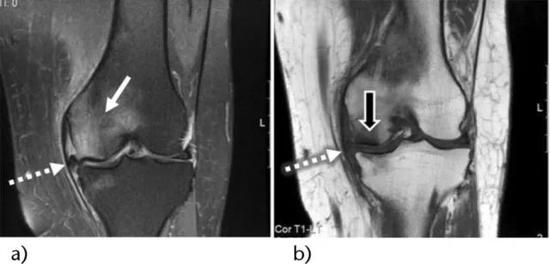

骨髓水肿(bone marrow edema,BME)在临床医生没有充分认识前,常被误诊和漏诊,随着核磁共振成像(MRI)技术的应用普及,诊断准确率得到了有效提高。如果把骨头比作一根木头,那么这根木头外观没有断裂,但里头的木头纤维断裂了,骨髓水肿实际上是构成骨头的骨小梁结构断裂出血,可以理解为微骨折,又称骨挫伤。

如果你的膝痛持续存在,并且并无好转,跑步还使得膝痛不断加重,那么最正确的处理方式就是到医院检查,对于医生来说,往往也无法判断你的膝痛是不是骨髓水肿造成的,但医生会通过询问病情并通过检查进行准确诊断。对于骨髓水肿来说,最有效精准的诊断手段就是核磁共振检查。核磁共振图像显示骨髓异常十分敏感,可以明确骨髓水肿的范围和严重程度。

如果存在持续的关节压力,比如跑步、爬山、越野跑、下蹲等等,那么这个病不仅不会好,甚至还会加重,只要经过足够休息,减少负重,那么该病一般不需要其他治疗手段,就能养好,时间多长呢?完全休息2-3个月。